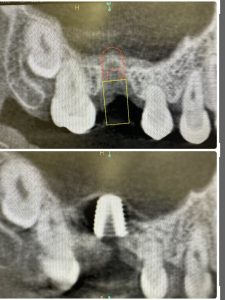

私は、朝からインプラント3本スキャナー印象

昼間からは、危ない動脈近接のソケットリフト

抜歯後2ヶ月待ちオペ、EMDとボナークのお陰です

違いが、分かるかなあ?